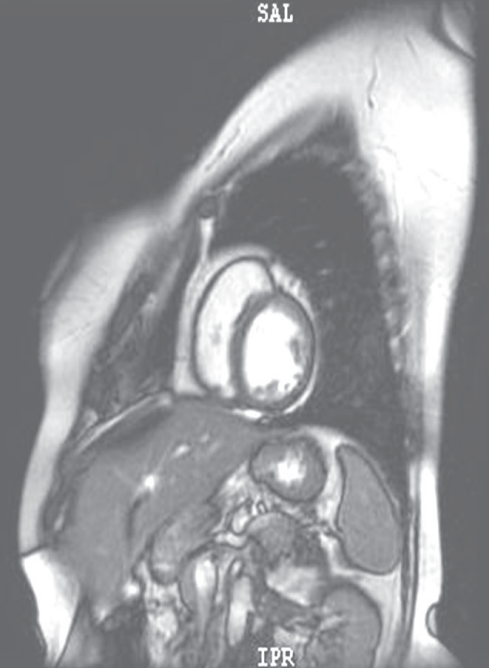

摘要:關(guān)于擴張性心肌病的最新治療,小巷深處的隱藏寶藏正逐漸為人們所發(fā)現(xiàn)。通過先進的醫(yī)療技術(shù)和方法,擴張性心肌病的治療取得了新的進展。這些治療方法旨在改善心臟功能,提高患者生活質(zhì)量。小巷深處的醫(yī)療機構(gòu)或?qū)<铱赡茈[藏著寶貴的治療經(jīng)驗和方法,為尋求最佳治療方案的病患帶來希望。更多詳細信息需要進一步探索和研究。

擴張性心肌病是一種嚴重的心臟疾病,但“心之港灣”為你帶來希望,這里的專家團隊一直在深入研究擴張性心肌病的最新治療方法,并深知每位患者都渴望得到最佳的治療和關(guān)懷,他們努力不懈,為患者帶來生機和新生。

你將了解到最新的藥物治療、心臟康復(fù)計劃以及生活方式調(diào)整等方面的知識?!靶闹蹫场边€開展了一系列臨床試驗,為患者提供最新的治療方案,他們的治療方法全面且個性化,因為每個患者的狀況都是獨特的,所以需要因人而異定制治療方案。

除了專業(yè)的治療,“心之港灣”同樣注重患者的心理健康,他們深知疾病帶來的心理壓力,因此提供心理咨詢和心理治療服務(wù),幫助患者恢復(fù)信心,重拾生活的快樂。